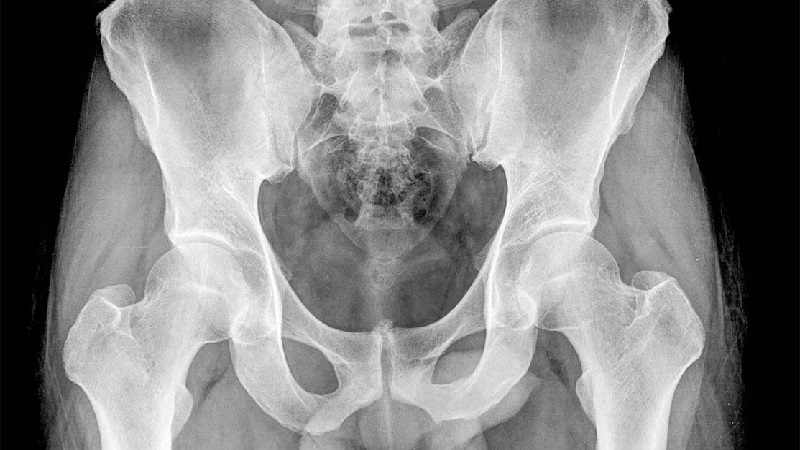

آمادگی رادیو گرافی ساده شکم؛ اشعه ایکس شکم با ارسال مقدار کمی تابش و پرتوهای انرژی الکترومغناطیسی به نقطه خاصی از بدن برای ثبت یک تصویر عمل می کند. ماده ای مانند استخوان متراکم است، بنابراین پرتو نمی تواند به آن نفوذ کند و این به صورت یک تصویر سفید روی عکس نشان داده می شود. موادی مانند بافتهای نرم و اندامها چگالی کمتری دارند و به نور اجازه میدهند به آنها نفوذ کند و در تصویر تیرهتر نشان داده شوند.

در زیر دلایلی وجود دارد که چرا معمولاً از اشعه ایکس لگن استفاده می شود.

آنها در تشخیص تعدادی از شرایط بسیار مفید هستند و روشی آسان و موثر برای تشخیص شکستگی یا شکستگی استخوان هستند.

اشعه ایکس شکم هیچ نقشی در تشخیص یبوست ندارد. این فقط یک آزمایش غربالگری برای تشخیص هر گونه مشکل استخوان، بافت یا اندام است، بنابراین نقش محدودی در درد شکم دارد. اشعه ایکس آنلاین اندازه، شکل و موقعیت اندام ها را نشان می دهد، بنابراین انجام ژست مناسب برای پوشش مناسب حیاتی است.